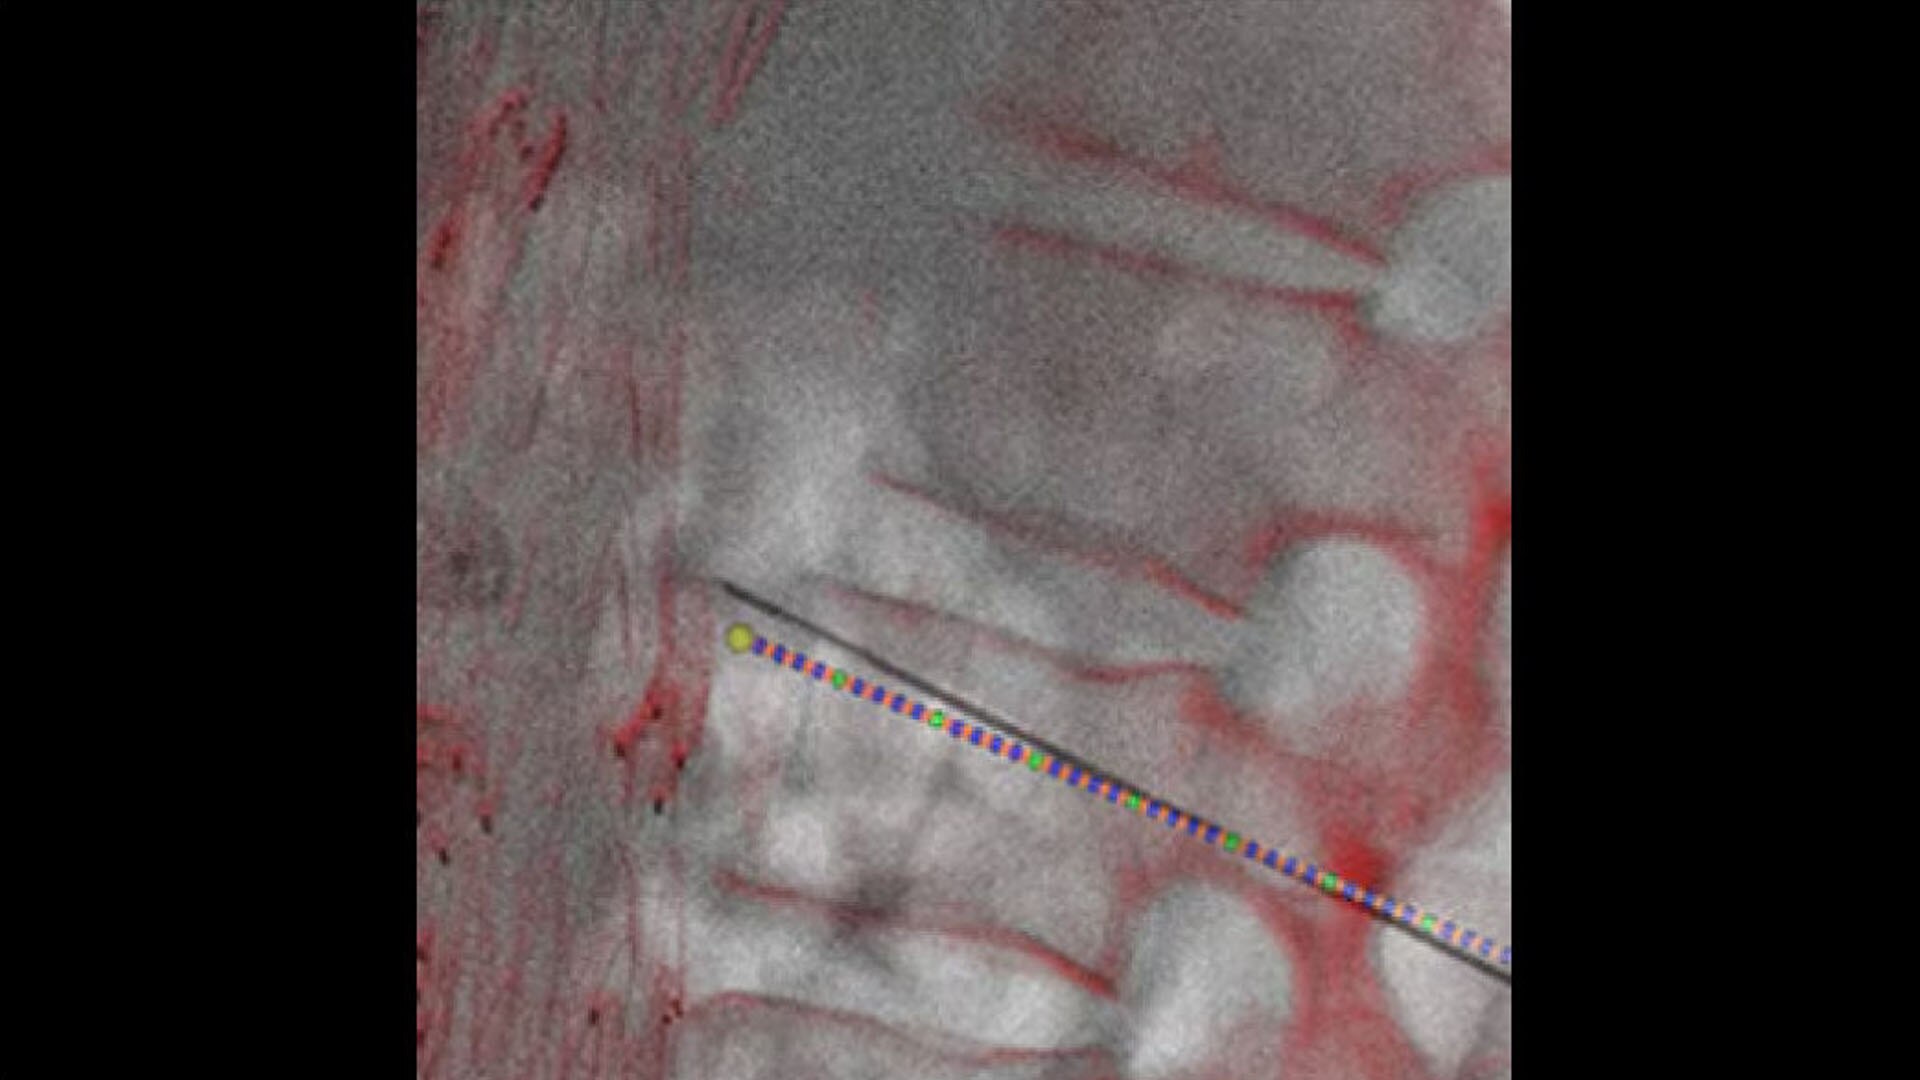

Plan

Define the pathway

Define optimal needle entry points and pathways directly on oblique CBCT cross sections.